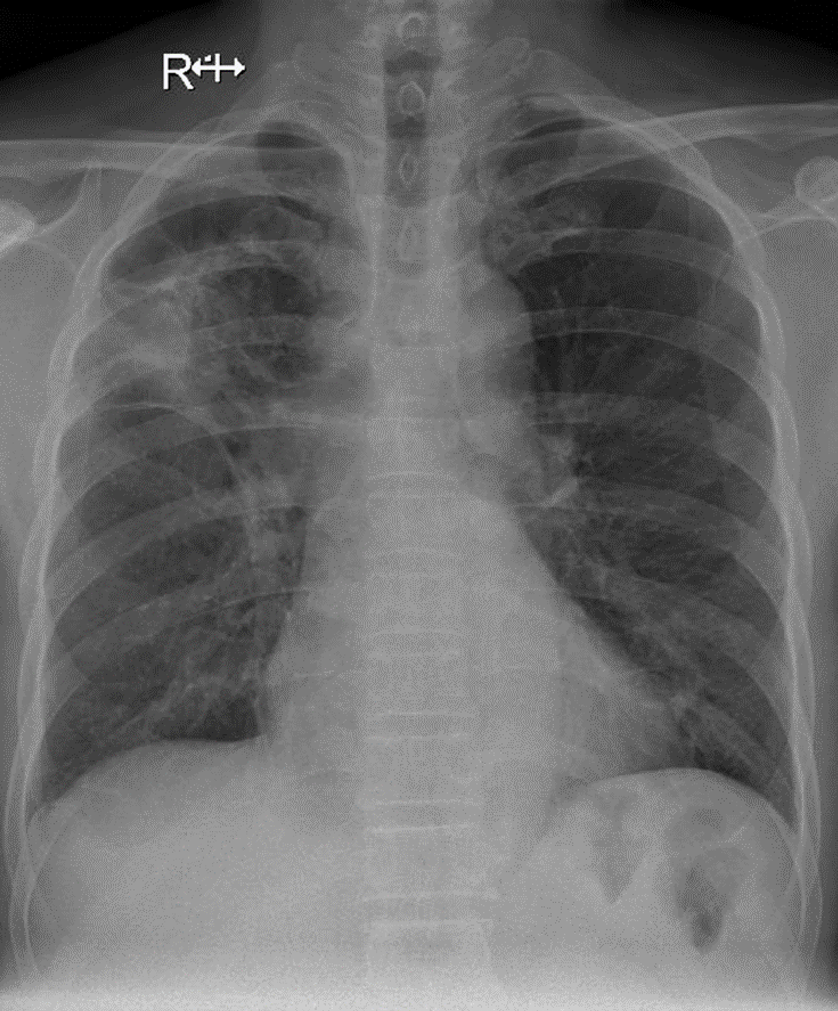

1-U thùy trên phổi (P) 2-Dày dính màng phổi (P)